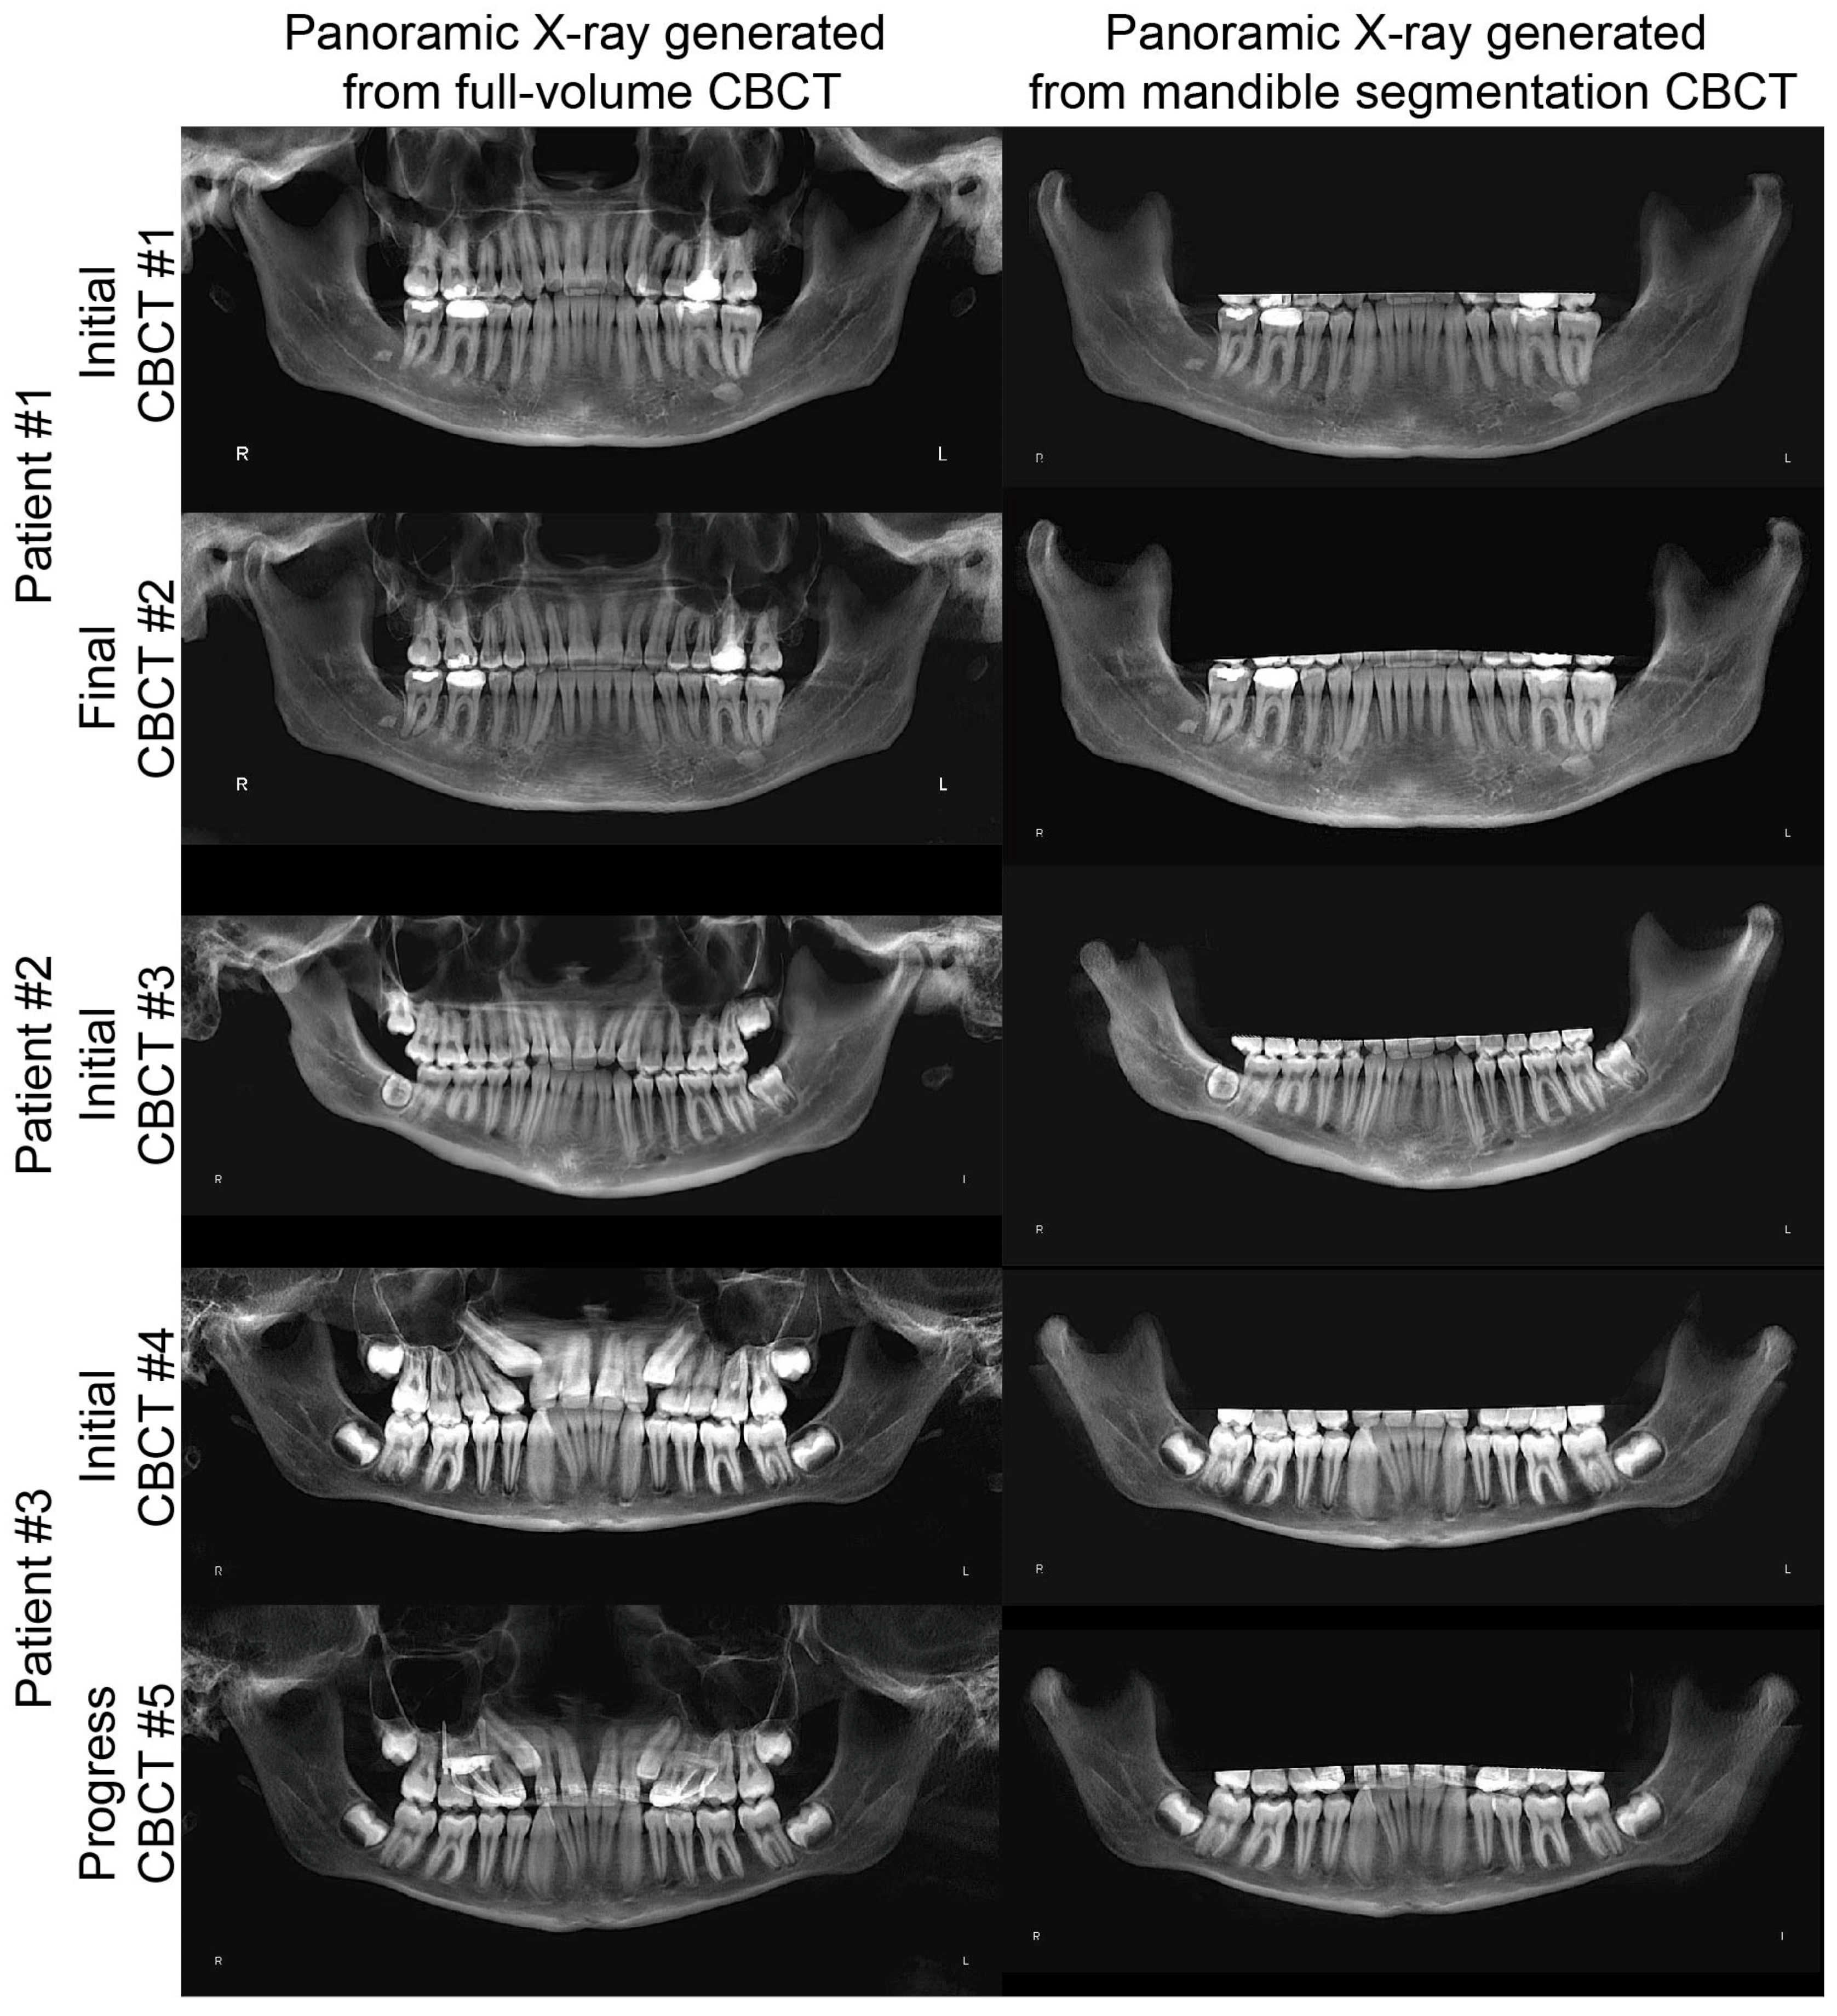

- In the “Sculpting tool” module, orient the CBCT to the right view, and sculpt the majority of the cranial and maxilla structures with the option “free form”, as shown in Figure 1A,B.

- Orient the CBCT to the bottom view in which the borders of the condyles are clearly visible. Sculpt the visible cranial and maxillary structures, as shown in Figure 1C,D.